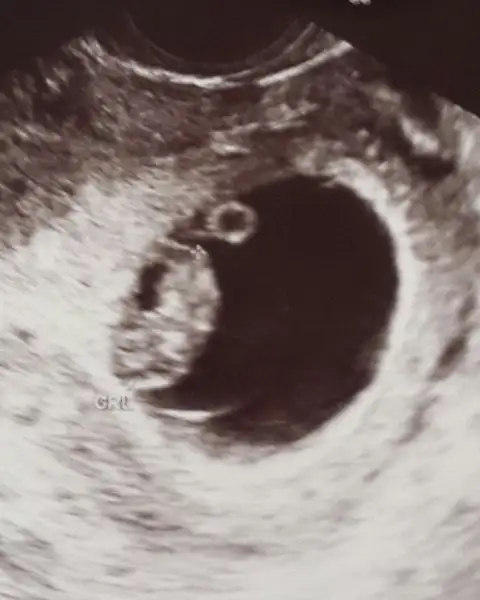

Havalianne__ kizz bude benim bebiki yorumla ikiside vajina yukardaki kizim 8 haftalik adagidaki simdiki 7 haftalik:)) ikisinide yükledim canim kizim erkek di keseye gore ??